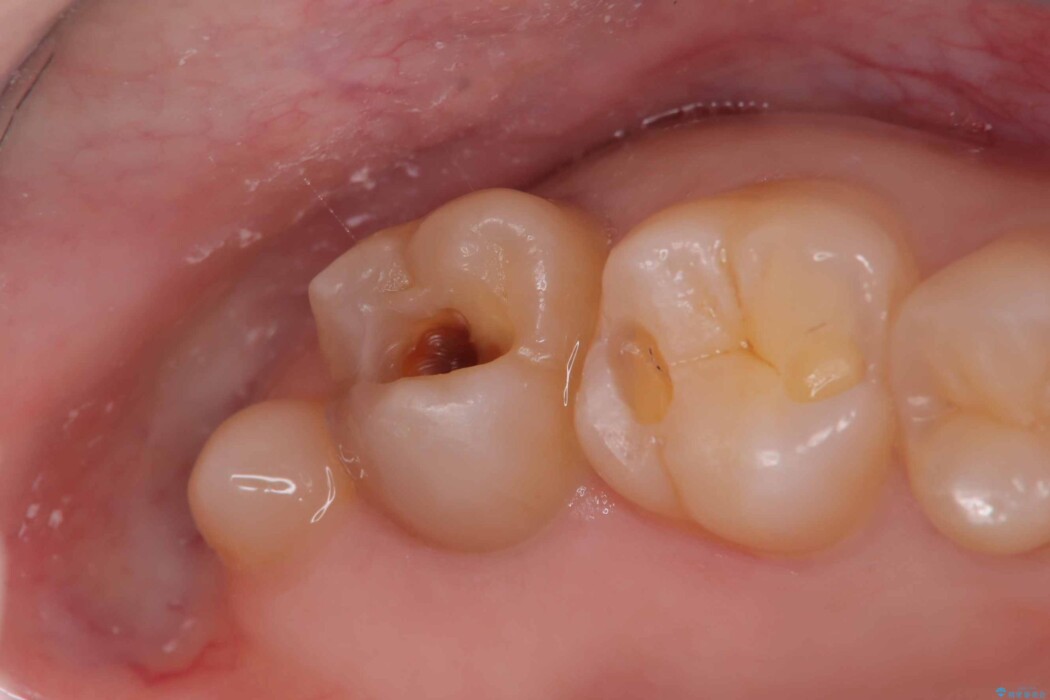

詰め物の下の見えない虫歯

以前に詰めた白い詰め物の内部で、虫歯の再発が確認されました。

まずは古い詰め物と虫歯を丁寧に除去します。